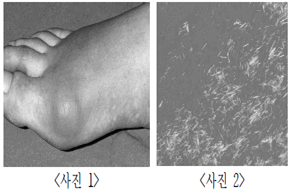

55세 남자는 오른쪽 엄지발가락(사진 1)의 통증을 호소하여 응급실에 내원하였다. 엄지발가락 관절의 윤활액을 분석한 결과, 요산결정체(사진 2)가 확인되어 A 질환이 확진되었다. 이 환자의 혈중 요산 수치를 낮추기 위한 약물로 가장 적절한 것은?